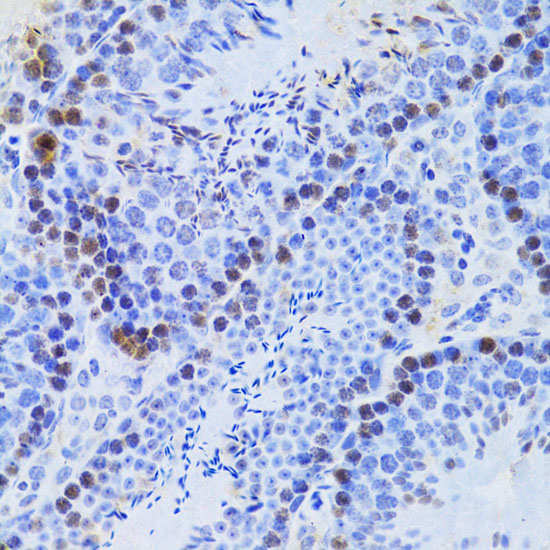

ApplicationWB, IHC, IF; Recommended dilution: WB: 1:500-1:2000, IHC: 1:50-1:100, IF:1:50-1:100